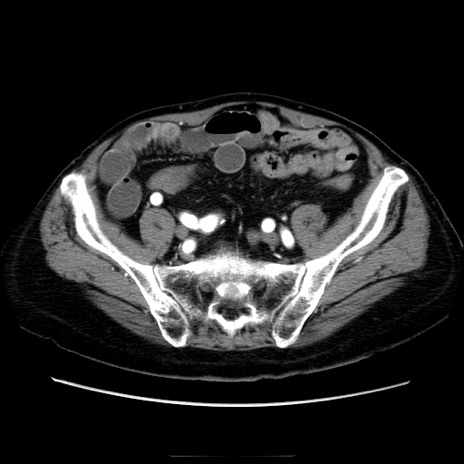

症例21(横断像)

【症例】70歳代男性

【主訴】腹痛

【現病歴】肝硬変・肝細胞癌にてかかりつけの方。約9時間前に食後より腹痛出現。症状が徐々に増悪し、嘔吐出現したため来院。

【既往歴】肝硬変、肝細胞癌(RFA、TACE後)

【身体所見】意識清明、表情苦悶様、BT 36℃、BP 129/78mmHg、P 88bpm、SpO2 97%(RA)、右上腹部から心窩部にかけて圧痛あり、反跳痛なし、筋性防御あり。

【データ】WBC 5800、CRP 0.16